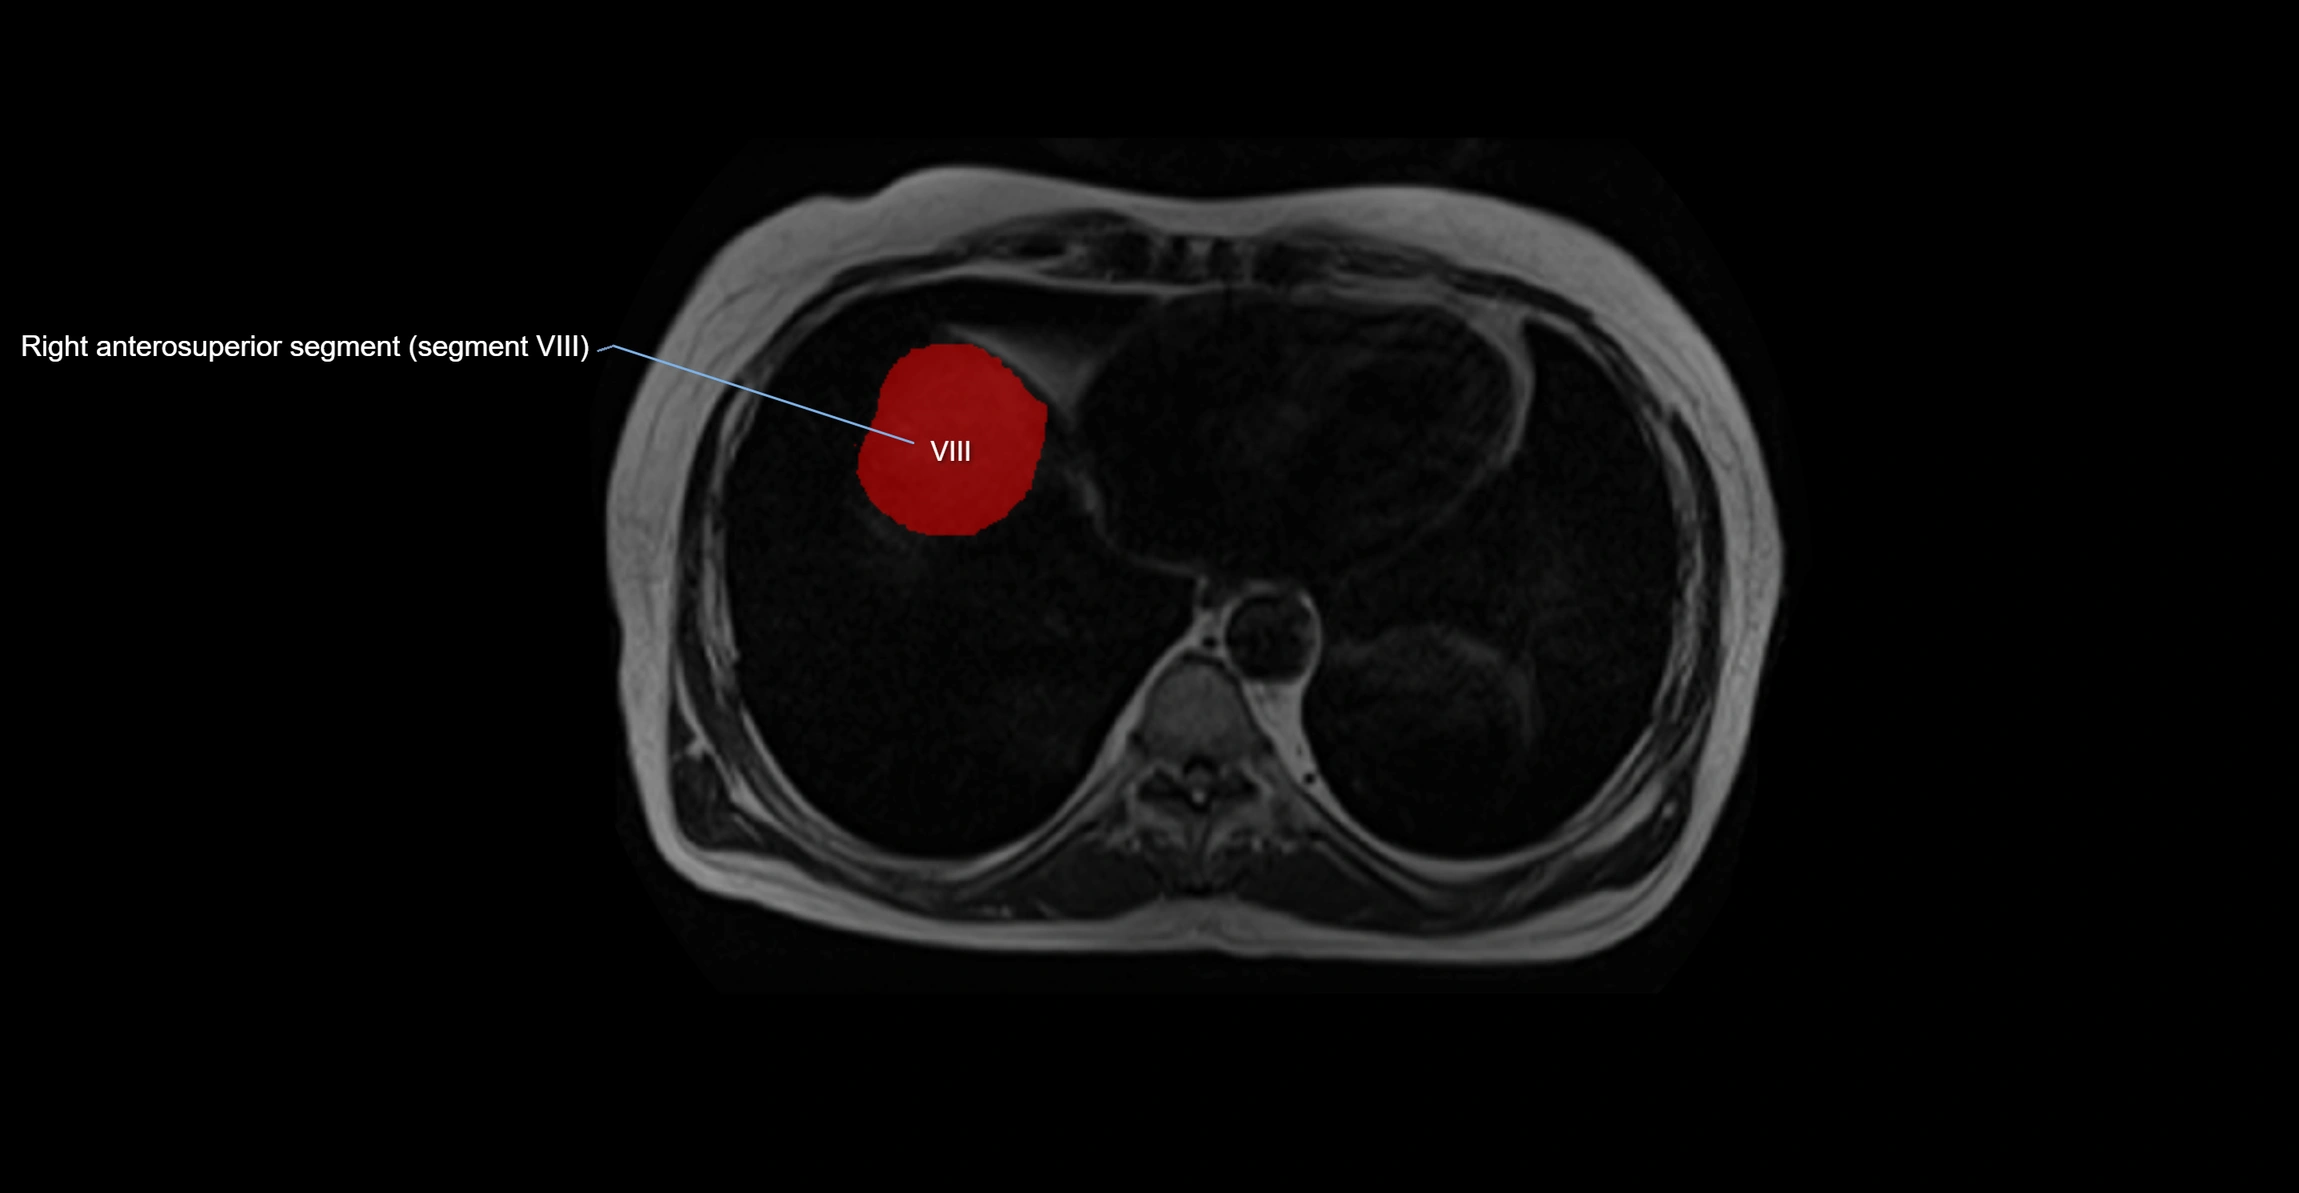

The caudate lobe of the liver is a distinct anatomical subdivision of the liver, designated as segment I in Couinaud’s classification. It lies on the posterior surface of the liver, between the fissure for the ligamentum venosum (left boundary) and the groove for the inferior vena cava (IVC) (right boundary). Superiorly, it is related to the posterior liver surface, and inferiorly it is separated from the left lobe by the porta hepatis.

The caudate lobe is unique because it receives dual portal venous and arterial inflow from both the right and left portal veins and hepatic arteries. It also has independent venous drainage directly into the IVC via multiple small hepatic veins, unlike other lobes that drain through the three main hepatic veins.

This anatomical autonomy makes the caudate lobe especially significant in liver surgery, transplantation, and hepatic venous outflow obstruction syndromes (e.g., Budd–Chiari syndrome). Enlargement of the caudate lobe is a characteristic imaging feature in chronic liver disease and cirrhosis.